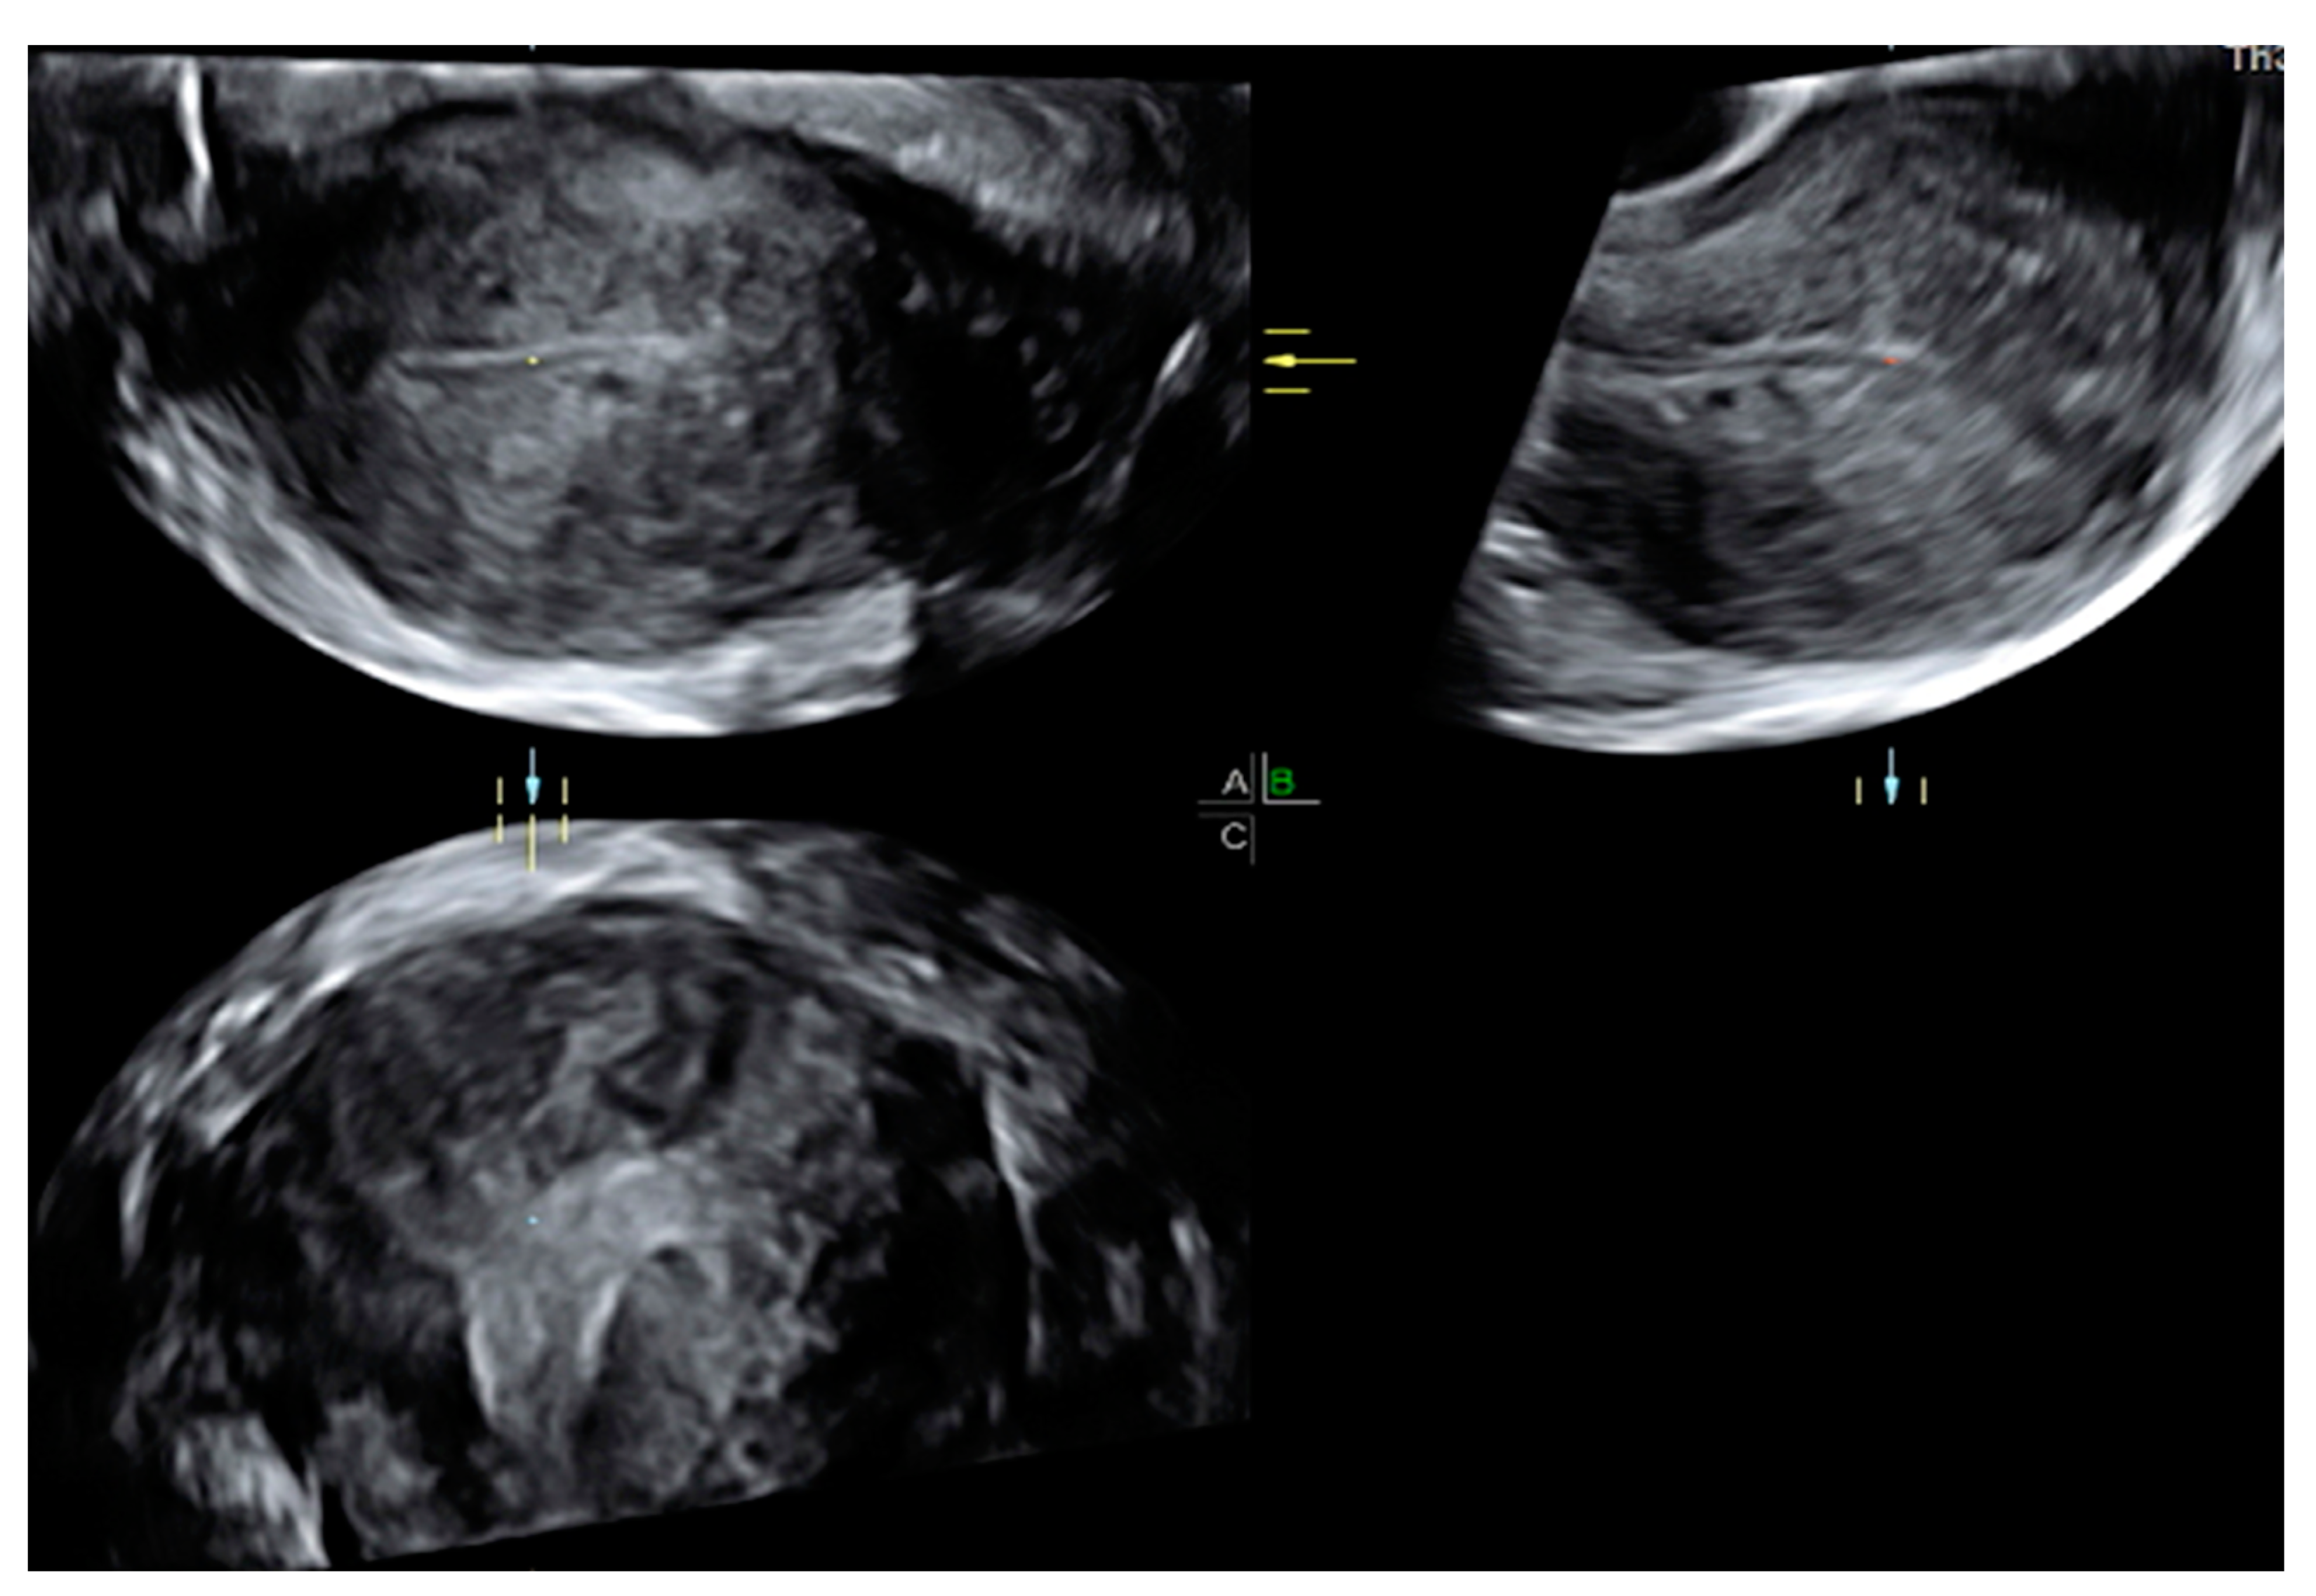

2.1. Ultrasound Diagnosis

- Myometrial cysts and intramyometrial cystic formations of any size (presence of a hyperechogenic halo is not mandatory). The contents could be anechoic, low-level, ground glass or of mixed echogenicity and may be surrounded by a hyperechogenic rim. Doppler can be used for differential diagnosis between blood vessels and myometrial cysts;

- Hyperechogenic islands with intramyometrial hyperechogenic areas within the myometrium that have no connection with the endometrium (regular, irregular, or ill-defined);

- Echogenic subendometrial lines and buds with hyperechogenic subendometrial lines or buds perpendicular to the endometrial cavity in a continuum with the endometrium, disrupting the junctional zone (JZ). On the other hand, the diagnosis of adenomyosis remains uncertain in cases of the presence of only indirect signs, including uterine wall asymmetry, translesional vascularity, JZ changes, fan-shaped shadowing, and globular uterus (Table 1).

- Irregular JZ with a poorly distinguishable endometrial–myometrial border;

- Disrupted JZ, possibly caused by focal or diffuse infiltration of the JZ by endometrial tissue. Uterine contractions may also give rise to apparent irregularities of the JZ or affect wall thickness;

- Alterations of the JZ due to subendometrial hyperechogenic lines and buds, ultrasound signs of focal adenomyosis infiltrating the JZ [26].